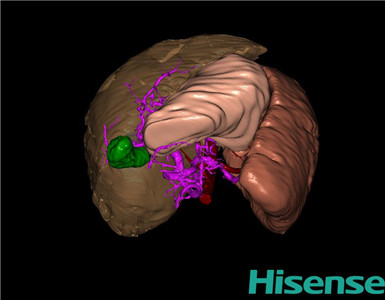

CT结果输入海信CAS系统后行3D重建及手术规划后,行手术治疗,术中证实为先天性门脉高压:

术前三维重建及手术方案设计:

将0.625mm双源薄层CT资料的静脉期和动脉期Dicom格式文件导入海信CAS系统。

通过调节窗宽窗位调整CT序号,对肝实质,胆囊,下腔静脉,肿瘤,肝动脉、门静脉及肝静脉等进行三维重建;系统自动计算肝脏体积。

术前三维重建:

重建图片